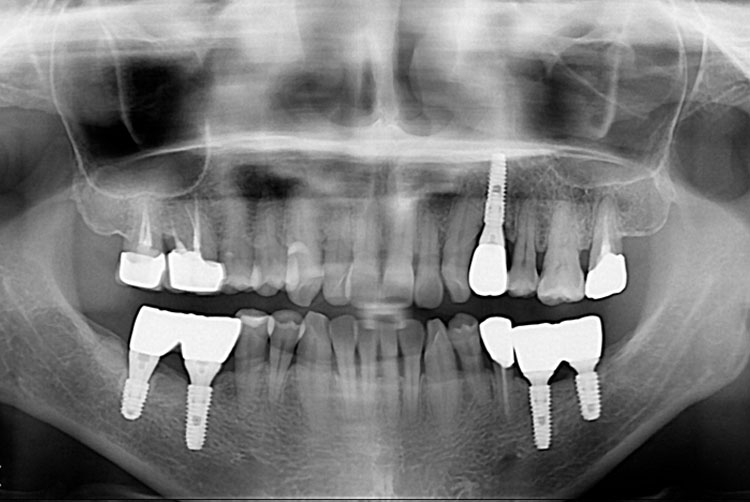

[임플란트] 임플란트

2020-09-23 81

치료전 : 2016-09-08

세종치과는 많은 환자와 다양한 케이스를 바탕으로 항상 편안한 임플란트 수술을 제공하고자 노력하고,

오래동안 튼튼히 쓸 수 있는 임플란트 수술을 가장 큰 목표로 삼고 있습니다.